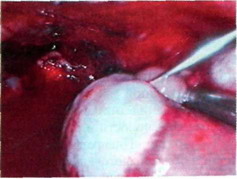

Под визуальным контролем разрушают все спайки, чтобы максимально выделить легкое. С париетальной и висцеральной плевры механически удаляют гнойно-фибринозный налет желеобразной консистенции толщиной от 2 до 100 мм (рис. 27-8).

Рис. 27-8. Удаление гнойно-фибринозного налета с париетальной и висцеральной плевры.